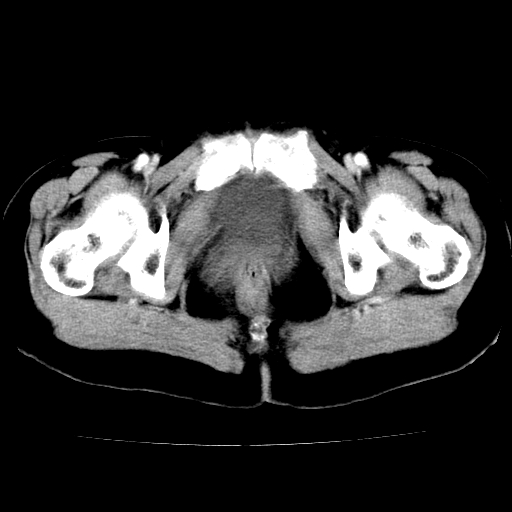

标题: CT24785:女,62岁,发现下腹部肿物半年。 [打印本页]

标题: CT24785:女,62岁,发现下腹部肿物半年。

女,62岁,发现下腹部肿物半年,下腹部不适。

老年女性患者,盆腔囊实性占位,ct增强不均匀强化,未见壁结节,未见腹水及盆腔积液,考虑附件囊腺瘤可能性大!

考虑肠系膜间质肉瘤或脐尿管癌可能性大。

考虑回肠间质瘤,不排除卵巢癌可能。

该年龄性别首先考虑平滑肌肉瘤可能性大,其他待排除。

考虑子宫平滑肌肉瘤可能性大。